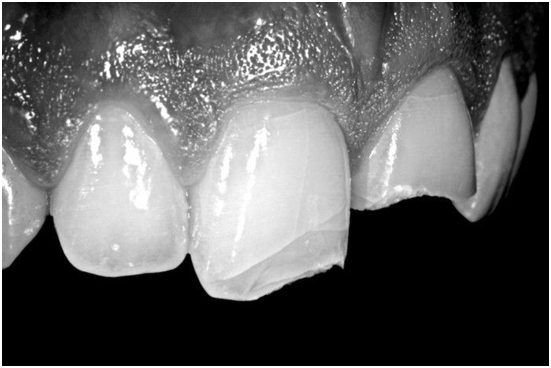

图22. 精确的位置可以通过牙齿表面的自然曲线来确定。